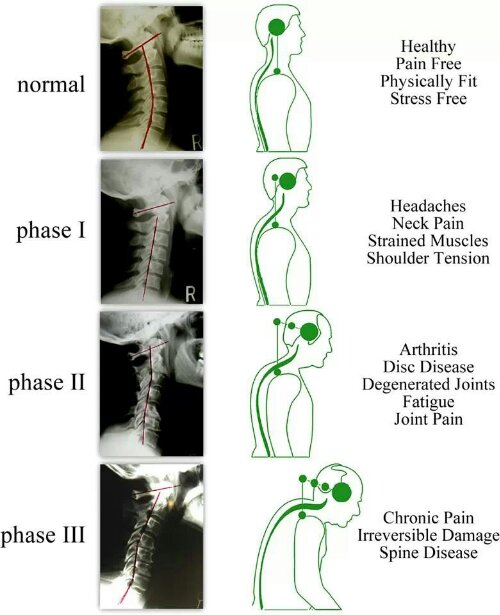

HWS Syndrom – Ursachen | Symptome | Behandlungen

HWS-Blockade lösen Übungen für die Halswirbelsäule + Video

Pin auf anatomie

HWS Haltung und Probleme – Chiropractic in Meerbusch bei Düsseldorf

HWS-Syndrom: Symptome und Behandlung

HWS-Syndrom behandeln: Ursachen, Behandlung und Übungen | Hws syndrom …